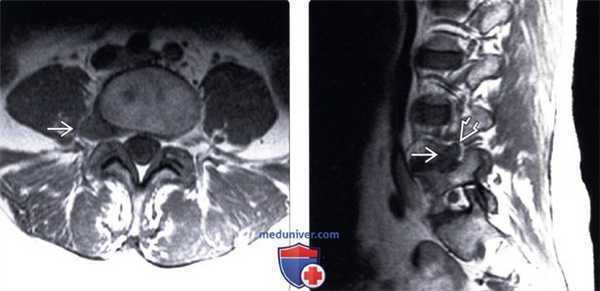

(Слева) Т1-ВИ, аксиальный срез: крупное мягкотканное образование, сообщающееся с межпозвонковым диском L4-L5 и распространяющееся в правое межпозвонковое отверстие и экстрафораминальные мягкие ткани.

(Справа) Т1-ВИ, сагиттальный срез: крупная латеральная и фораминальная грыжа диска, замещающая собой фораминальную жировую клетчатку и смещающая корешок L4 вверх.